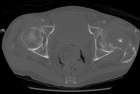

67 year old male with c/o L hip pain for one month presents with sudden severe increase in pain and inability to bear weight.